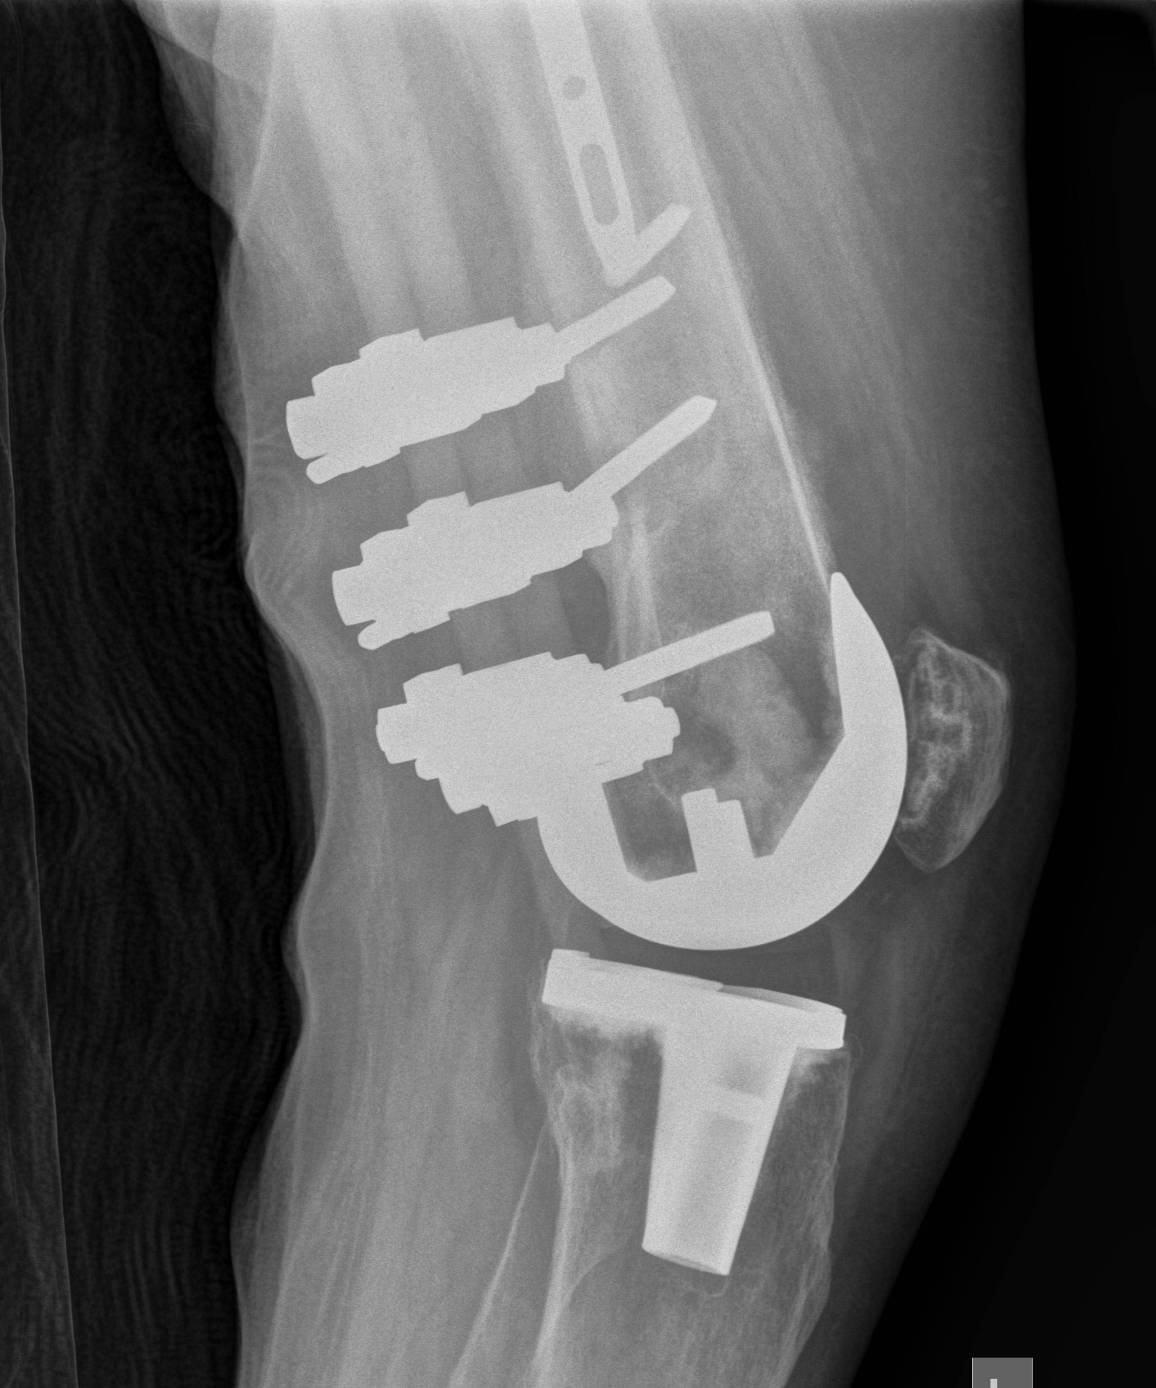

2. NOF (Neck of Femur) + Femoral shaft fracture

Must pay attention first to meticulous NOF ORIF

Options

1. Pin and Plate NOF / Retrograde Nail

2. Pin and Plate NOF / Plate femur

3. Reconstruction Nail

- difficult to anatomically reduce NOF

- increased incidence NOF non union

Results

Ostrum et al. CORR 2014

- 95 cases treated with proximal screws / sliding hip screws inserted first

- retrograde IMN second

- 98% union rate femoral neck

- 91% union rate femoral shaft